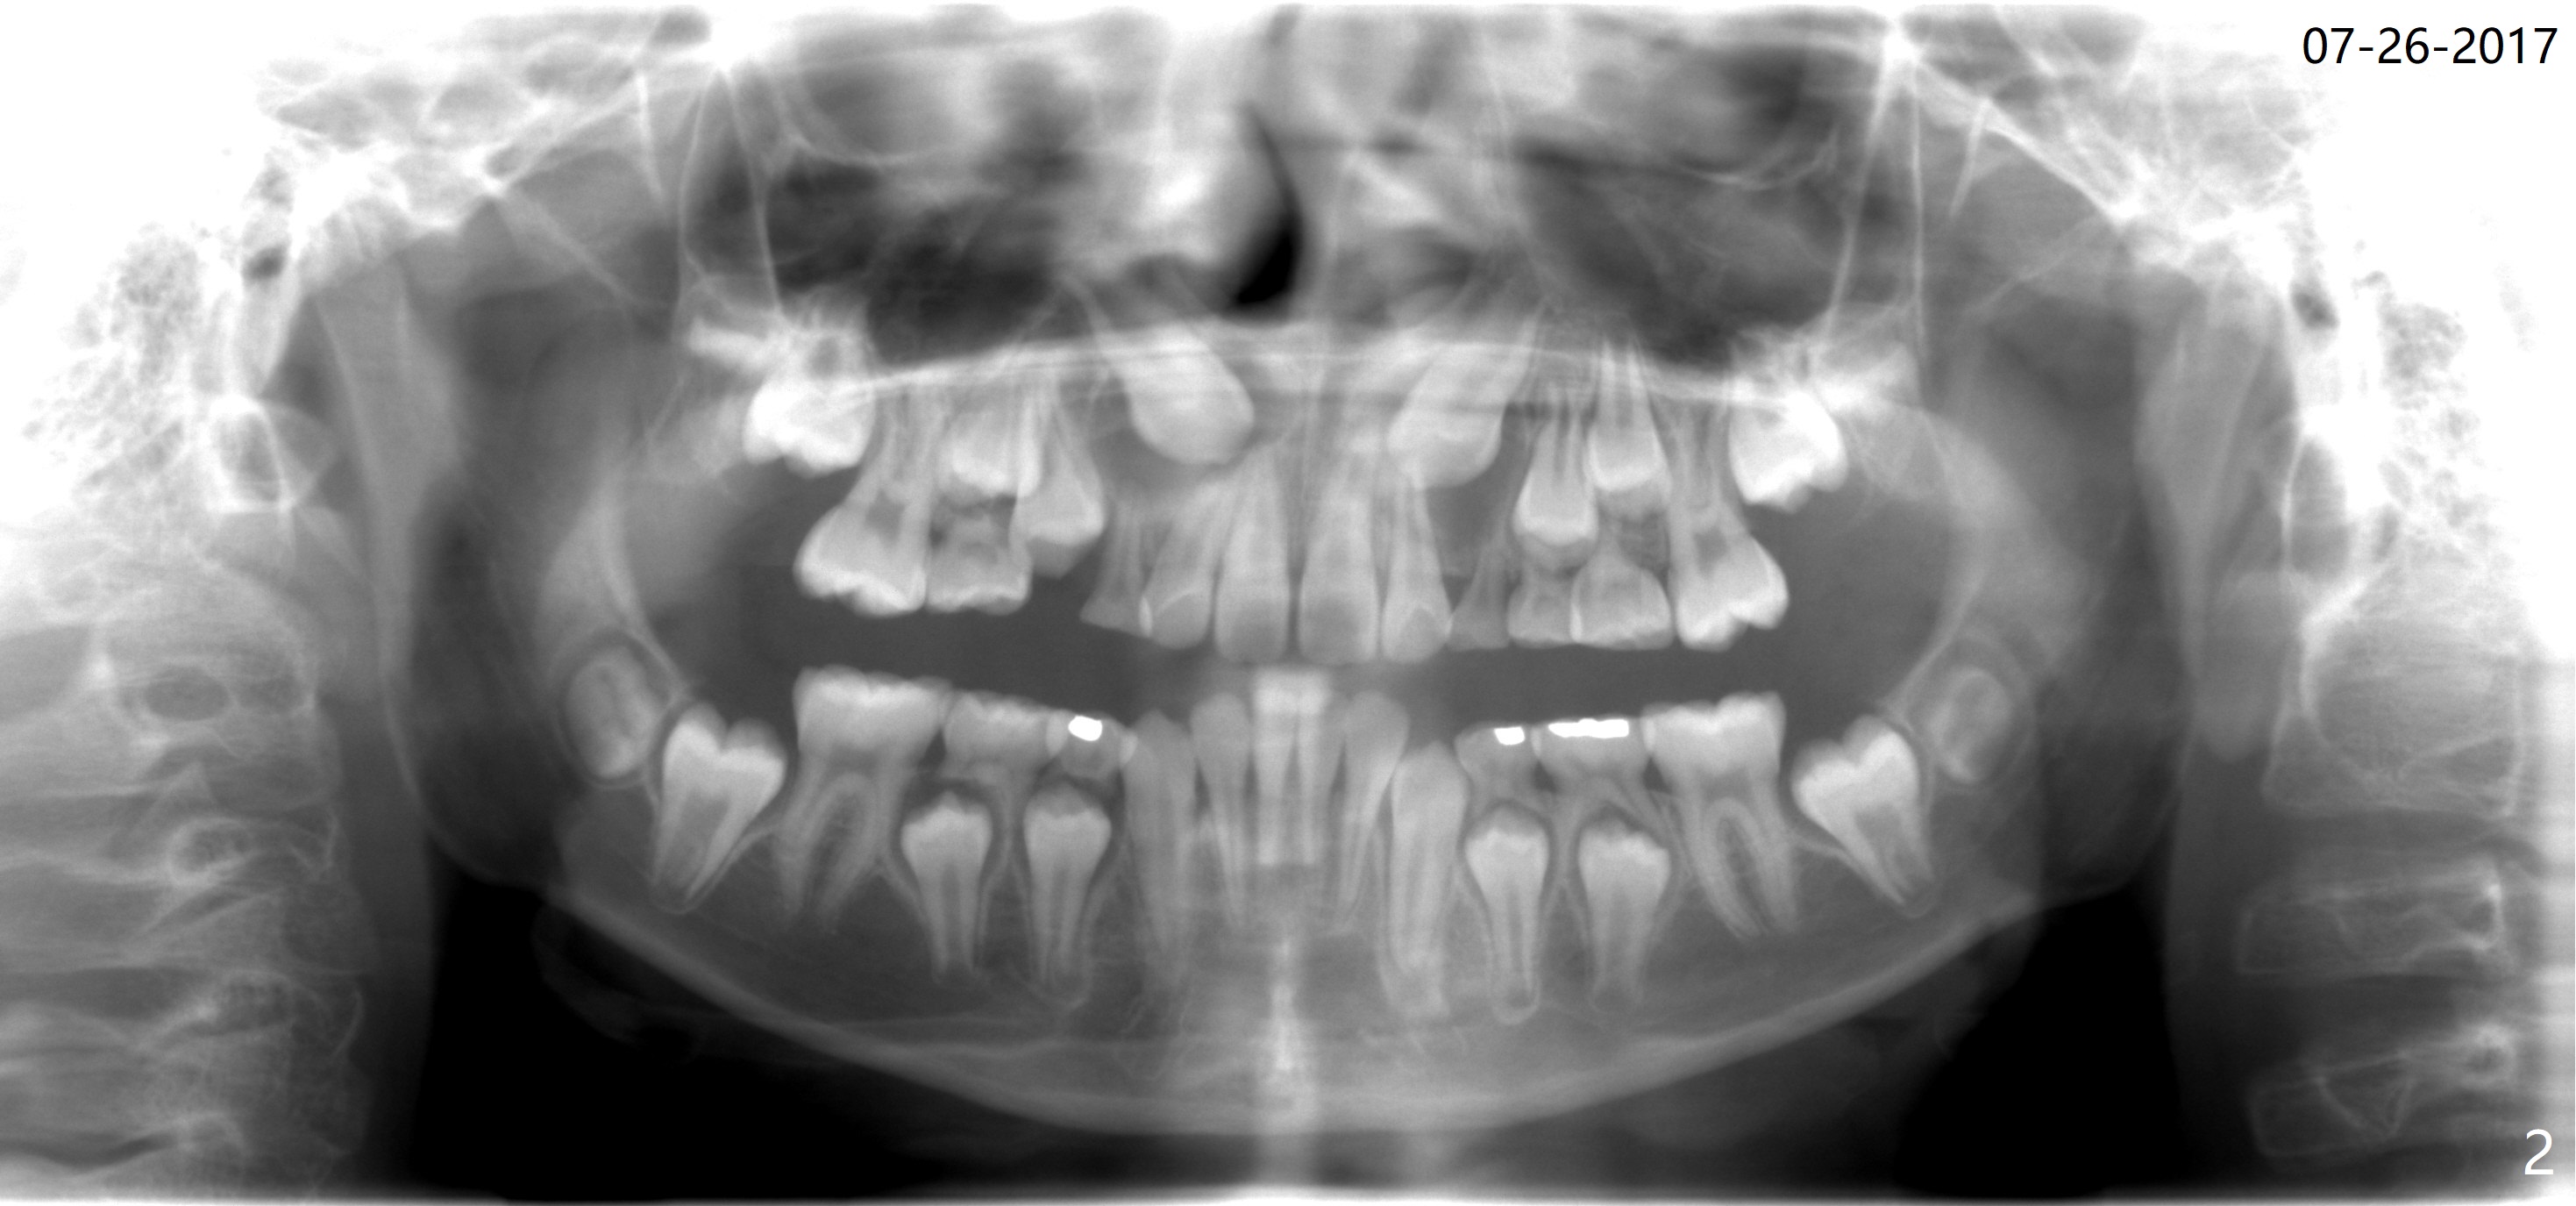

A 13-year-old boy with Class III malocclusion returns with mother from an orthodontic office for extraction of the tooth H with panoramic X-ray taken last year (Fig.1). An interesting finding was present, but not diagnosed a year earlier (Fig.2).

A cystic lesion around each of the impacted permanent upper canines. A normal dental sac or dentigerous cyst?